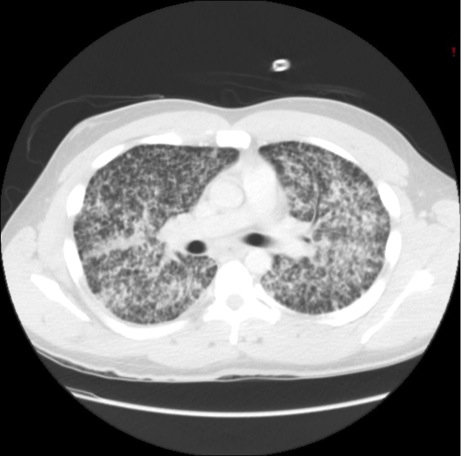

Figure 2: Computed Tomography (CT) of the chest demonstrated diffuse micro-nodular infiltrates throughout both lung fields without associated lymphadenopathy